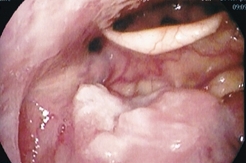

図1:舌根にできたがん

中咽頭とは口を開いて覗き込むと見ることができる「のど」の部位のことです。その中には扁桃(腺)や舌根(舌の根元)、口蓋垂(のどちんこ)などがあります(図1)。そこにできるがんを中咽頭がんと呼びます。中咽頭がんの原因には多量の喫煙や飲酒が古くから知られています。最近になり、その他の原因としてヒトパピローマウイルス(HPV)が関与していることが分かり、日本でも中咽頭がんの約半数でHPVが原因のがんであることが分かってきています。